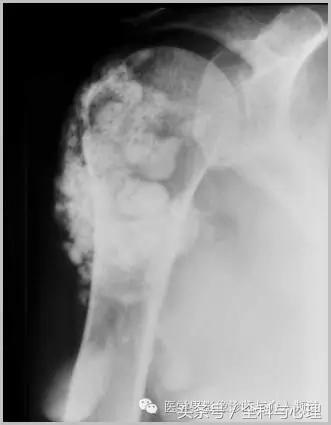

一、肿瘤样钙质沉着症

累及多个关节,范围较大,表现为多房囊状的高密度影。

原发性:罕见,多为家族性,多见于非洲裔美国人,钙磷正常。

继发性:多见于慢性肾功能不全患者。钙磷均有升高。

肿瘤样钙质沉着症